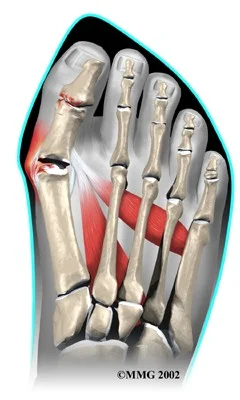

Hallux Valgus

- Definition: lateral deviation of the great toe (hallux) and medial deviation of the first metatarsal

Deformity / Bunion / medial deviation MT-1

Radiology - Hallux Valgus

- XR views:

- AP standing:

- Lateral deviation of big toe

- Increased varus of 1st MT

- Subluxation of MT-Phal. joint

Treatment - Hallux Valgus

Aim:

- Re-align the 1st metatarsal

- Correct valgus deformity of big toe

- Soft tissue balancing